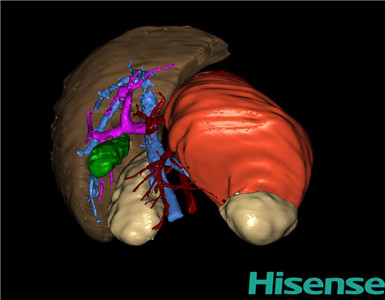

术前三维重建及手术方案设计:

将0.625mm双源薄层CT资料的静脉期和动脉期Dicom格式文件导入海信CAS系统。

通过调节窗宽窗位调整CT序号,对肿瘤,肝实质,胆囊,下腔静脉,肿瘤,肝动脉、门静脉及肝静脉等进行三维重建;系统自动计算肿瘤体积和肝脏体积。

模拟手术操作,自动计算切除肿瘤体积。肝脏体积为573.4ml,肿瘤体积为375.6ml,肿瘤体积为肝脏体积的65.5%,通过比对3-4岁正常肝脏体积为522.63±121.24 ml,通过术前模拟手术,精准判断切除后剩余肝脏体积能耐受,避免肝衰竭发生。

术前三维重建:

重建图片